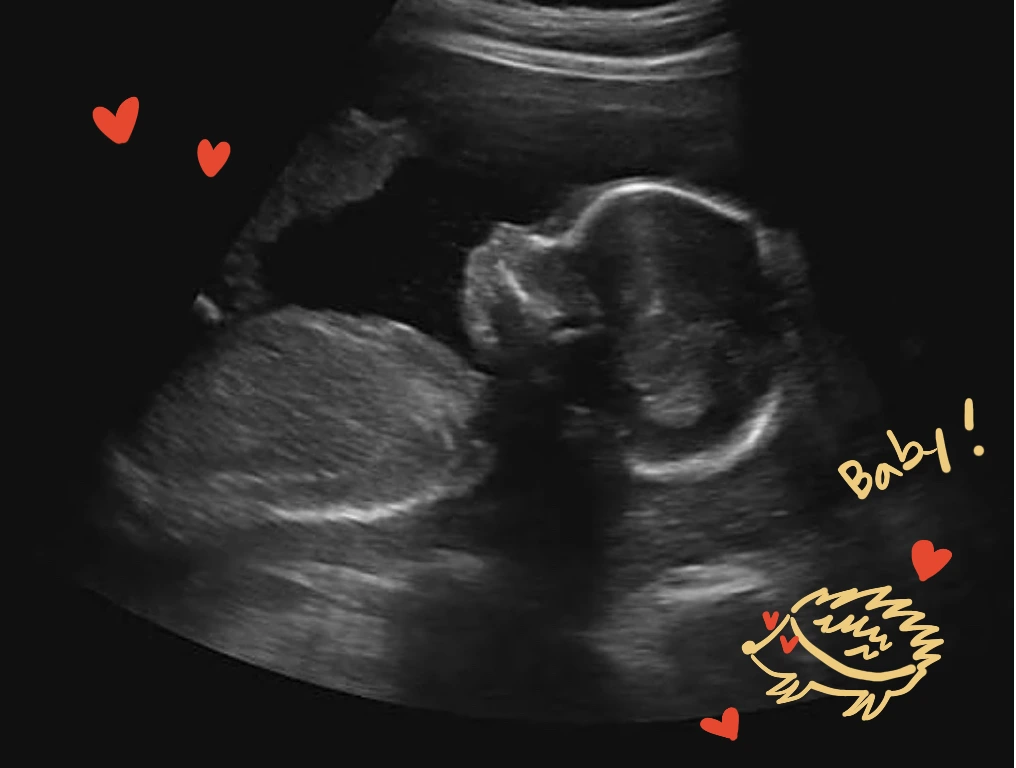

뱃속 아기가 커가며 반드시 받아야 하는 검사들이 있다. 임신을 확인하고 종이 한 장을 받았다. 주 차별 검진에 관한 안내. 기본적인 초음파, 혈액검사 같은 정기 검진 후 12주에 접어들면 첫 기형아 검사를 한다. 계속 정기 검진을 이어가며 20주에는 정밀 초음파, 24주 임신성 당뇨 검사 그리고 막달 검사와 태동 검사로 이어진다.

감동이가 작은 콩 같던 시절엔 그에 반비례하는 커다란 두려움이 있었다. 아기를 낳으면 손가락 발가락이 모두 열 개인지 확인부터 한다던데, 그 맘을 꼭 알겠다. 아기가 사람의 형태를 제대로 갖춰가며 커갈 것인지에 대한 막연한 두려움. 만화책을 너무 많이 봤던 어미는 팔이 세 개고, 눈이 한 개인 외계인들을 떠올리며 혹시나 뱃속에 사람이 아닌 다른 형태의 생명이 있는 건 아닌지 터무니없는 걱정을 시도한다. 시간이 지나 감동이가 제법 사람의 모습을 띠게 되면서 기우의 크기는 점점 줄어갔지만, 어렴풋한 불안은 끊어 낼 수 없다.

6개월에 들어서면 30분 정도 정밀 초음파를 받게 된다. 제법 배가 나오기 시작할 때라 천장을 보고 바로 눕는 것도 힘이 들지만, 아기가 어느 정도 자란 만큼 전체적인 구조적 이상을 확인 할 수 있다니 참고 견뎌야 한다. 5분 내외로 살피던 초음파와는 다르다. 미간, 인중처럼 세밀한 부분까지 헤아려보며 태아에게 이상이 없는지 꼼꼼하게 확인한다. 작은 손가락, 발가락까지도 눈으로 볼 수 있으며, 꽤 긴 시간 아기를 담뿍 관찰할 수 있기에 늘 뱃속이 궁금한 어미에겐 아주 좋은 기회다.

이상 소견 또한 없음. 기분 좋게 정밀 검사를 마쳤고, 병원에서는 30분간의 기록을 모두 저장 장치에 담아 주셨다. 하나씩 늘어가는 초음파 사진과 영상들이 앨범에 쌓여간다. 남들보다 자주 병원에 갔던 탓에 그 양이 상대적으로 많으니 감동이는 복도 많다.

8개월 차. 선택사항인 입체 초음파를 예약했다. 해도 그만 안 해도 그만인 검사지만 세상에 나올 아기의 실제 모습을 미리 엿볼 수 있는 절호의 기회다. 이미 검색을 통해 다른 아기의 입체 초음파 사진을 여러 장 감상했기에 부푼 기대를 안고 병원으로 향했다. 과연 우리 감동이는 어떤 모습을 하고 있을까? 매번 까만 초음파로 보던 납작한 평면이 아닌, 입체적으로 드러날 아기의 얼굴. 가슴이 콩닥거린다.